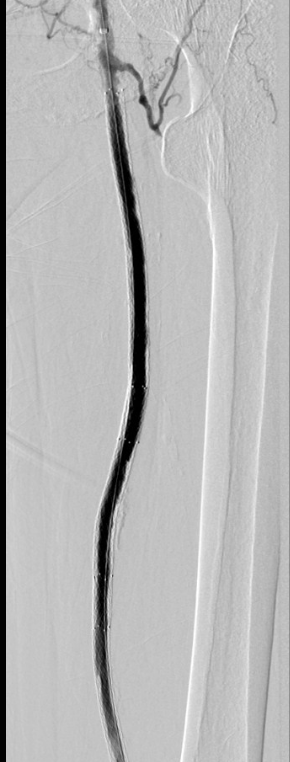

此时造影显示血流速度已得到明显的改善。最后再用药物涂层球囊扩张股动脉病变段,再次造影见血流通畅,经过4小时后,手术顺利完成。

术后造影